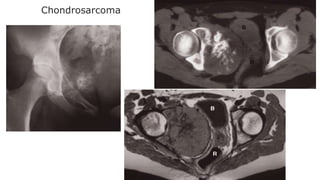

Chondrosarcoma

30–50-year-old age group

Most commonly in the pelvic bones, scapulae, humeri and

femora.

A chondrosarcoma produces a lytic expanding lesion

containing flecks of calcium.

Itcan be difficult to distinguish from enchondroma, but it is

usually less well defined and may show a periosteal reaction.

A chondrosarcoma may arise from malignant degeneration of a

benign cartilaginous tumour